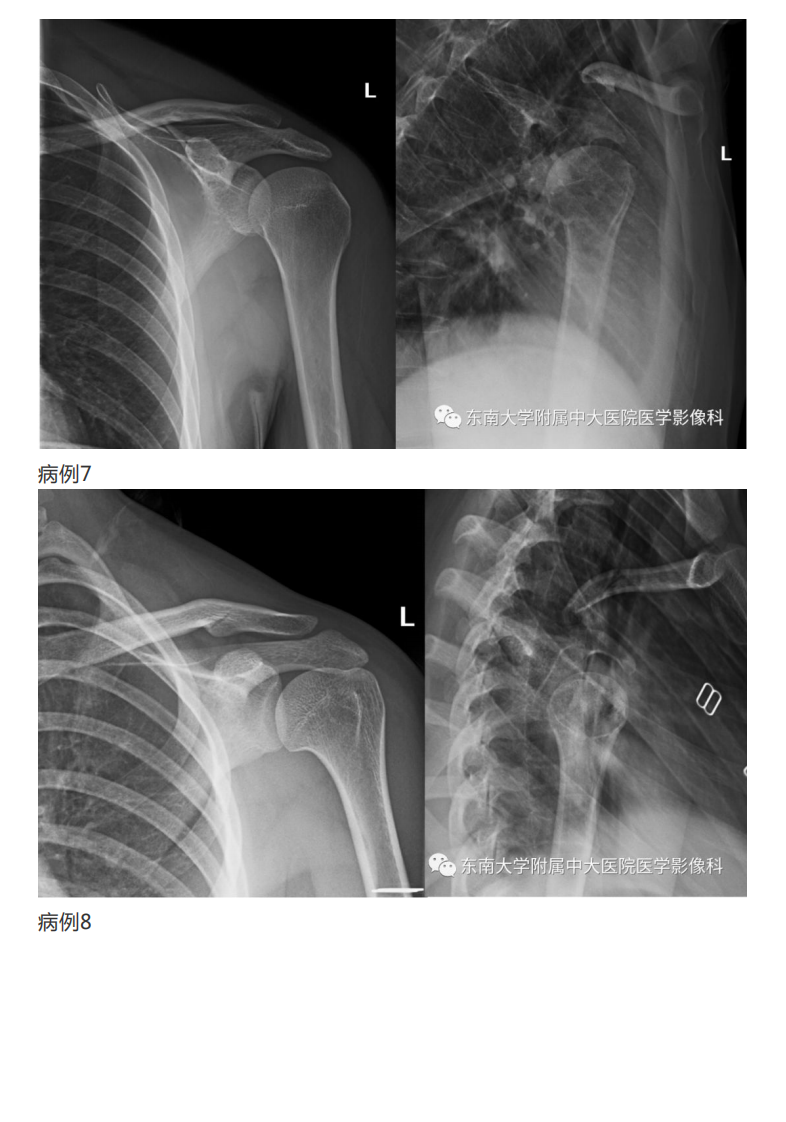

20190409_2【晨读结果公布】2019.04.08肌骨系统疾病.pdf